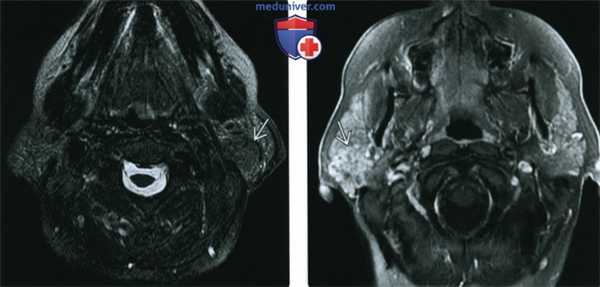

(Справа) На аксиальной МРТ (Т2 ВИ FS) в околоушной железе визуализируется опухоль неправильной формы со смешанным сигналом. С наружной стороны определяются кистозные участки, с внутренней - область с сигналом низкой интенсивности. Типоинтенсивный Т2 сигнал солидном компоненте опухоли характерен для МЭР.

(Справа) МРТ Т2ВИ FS, аксиальная проекция. Новообразование неправильной формы в правой околоушной железе. Сигнал смешанной интенсивности на Т2ВИ. Латеральнее видны кистозные участки с гиперинтенсивным сигналом, медиальнее - участок гипоинтенсивною сигнала. Для мукоэпидермоидною рака характерно наличие зон гипоинтенсивною сигнала на Т2ВИ.

(Слева) МРТ Т1ВИ, аксиальная проекция. В хвосте околоушной железы определяется округлое образование с четкими контурами и сигналом промежуточной интенсивности. Обратите внимание, что данное новообразование, мукоэпидермоидный рак низкой степени злокачественности, на изображениях без контрастирования легко отличить от окружающей ткани железы.

(Справа) МРТ Т1ВИ FS с КУ, этот же пациент. Определяется округлое образование с четкими контурами, которое практически неотличимо от окружающей паренхимы железы. Иногда введение контраста скрывает опухоли околоушной железы. Это происходит в том случае, когда сигнал от контраста оказывается равен сигналу жировой клетчатки железы.

(Слева) МРТ Т2ВИ FS, этот же пациент. Округлое образование с четкими контурами и сигналом низкой интенсивности. Сигнал низкой интенсивности нехарактерен для Т2ВИ, обычно он является признаком мукоэпидермоидного рака.

(Справа) MPT Т1BИ FS с КУ. Определяется дольчатое образование с четкими контурами, в толще которого имеются кистозные участки. В случае мукоэпидермоидного рака это может быть как одна крупная киста, так и множество мелких кист.